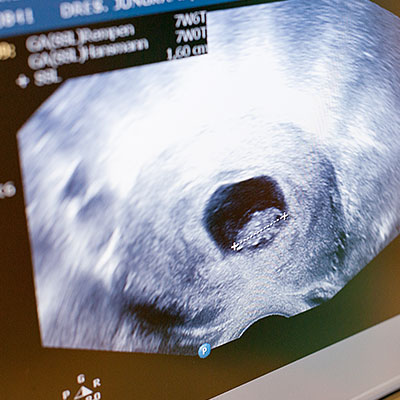

- Ultraschall in der Schwangerschaft

- Nackenfaltenmessung (Ersttrimesterscreening, zertifiziert nach der Fetal Medicine Foundation Deutschland e.V.)

- 3D Ultraschall